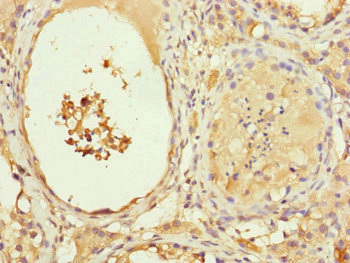

圖片:

應(yīng)用范圍:ELISA, IHC

Application Recommended Dilution IHC 1:20-1:200 -